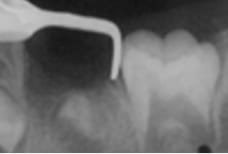

ディスタルシュー

6才臼歯が生える前に、手前の乳歯が抜けてしまった場合に装着します。

定期検診で経過をみて、6歳臼歯が生えてくる時期に装置をはずします。